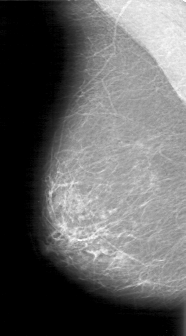

D_4047_1.RIGHT_CC

RIGHT_MLO LINES 5026 PIXELS_PER_LINE 2776 BITS_PER_PIXEL 12 RESOLUTION 43.5 NON_OVERLAY